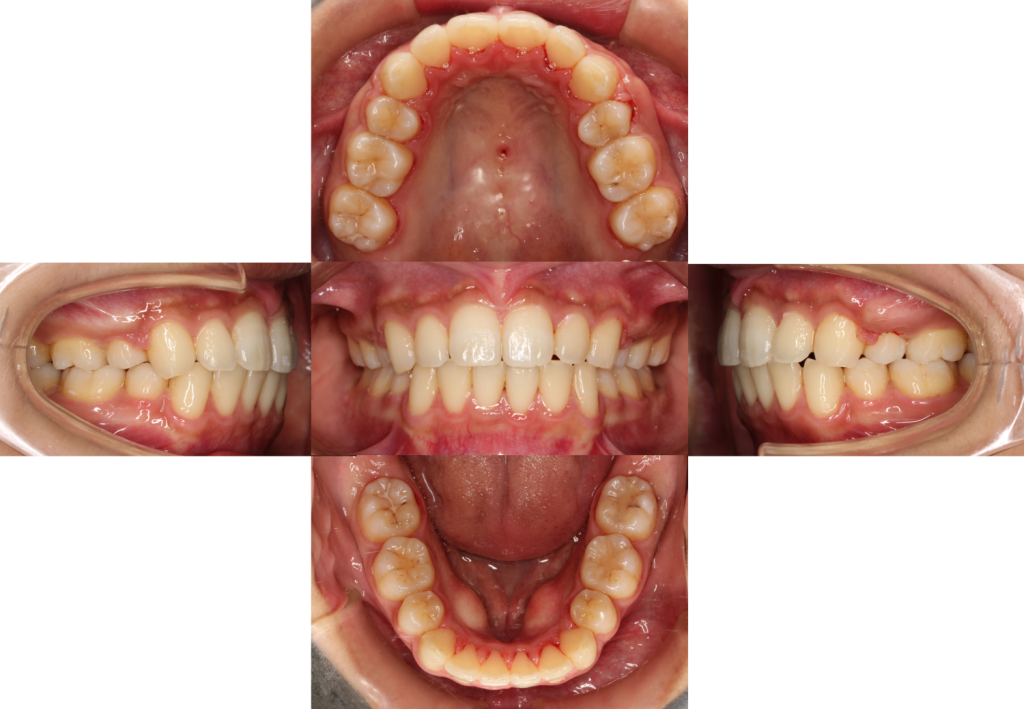

隙間が閉じきって、上下のバランスもキレイに整いました。

元々のお悩みだった、【口元の突出感と下の歯のガタツキも改善しました】

| 年齢層 | 20代 |

|---|---|

| 性別 | 女性 |

| 主訴 | 口元を下げたい・下の歯の叢生 |

| 治療費用 | 検査・診断:税込み38,500円/裏側矯正治療(リンガル矯正):税込1,397,000円 |

| 治療期間 | 約2年4か月(28回) |

| 抜歯 | 有(上顎両側4番、下顎両側4番) |

| 矯正の装置 | 検査・診断:税込38,500円/裏側矯正治療(リンガル矯正):税込1,397,000円 |

| 副作用、リスク | 歯肉退縮,歯根吸収,疼痛,咬合の違和感,装置の違和感,虫歯,歯肉炎 |